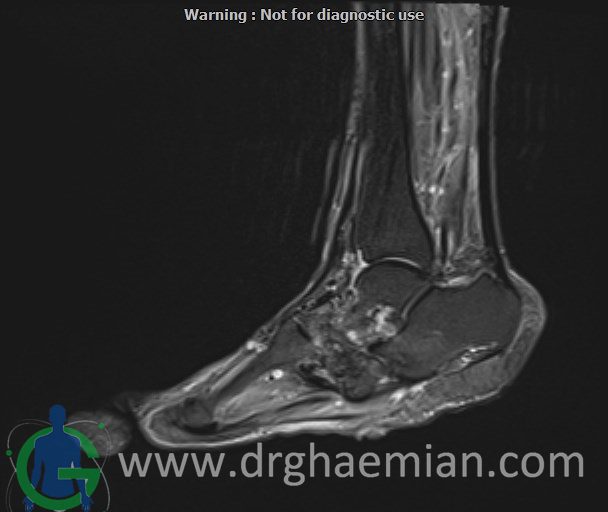

ام آر آی کف پا و انگشتان یک روش تصویربرداری پزشکی است که با استفاده از میدانهای مغناطیسی قوی و امواج رادیویی تصاویر دقیق و باکیفیتی از ساختارهای داخلی کف پا و انگشتان ایجاد میکند. این روش بدون استفاده از اشعههای مضر مانند اشعه ایکس انجام میشود و به پزشک کمک میکند تا با جزئیات بیشتری آسیبها، التهابها یا مشکلات دیگر را تشخیص دهد.در ان کیس یک پای بیمار مبتلا بهب بیماری دیابت دیده میشود.

MRI OF RIGHT FOOT

1.5 Tesla MR System

Multislice, multiplanar and multisequence MR images findings:

There is a skin ulcer in the plantar aspect of the foot, superficial to the midfoot, without obvious collection.

Destruction and erosion of the midfoot structures and articular spaces are seen, resulting in midfoot collapse.

T1 signal intensity of bone marrow in the midfoot region is preserved, and there is no imaging evidence of acute osteomyelitis; however, chronic osteomyelitis cannot be ruled out.

Abnormal high T2WI and low T1WI signal intensity are observed in the 5th proximal and distal phalanges, in association with a suspicious plantar site ulcer, highly suggestive of osteomyelitis in this area.

Other bones, joints, and soft tissues of the foot appear unremarkable.

Impression:

Plantar skin ulcer overlying the midfoot with no associated collection

Structural destruction and erosion of midfoot bones and articular spaces causing midfoot collapse, without definite signs of acute osteomyelitis, though chronic osteomyelitis cannot be excluded

Abnormal marrow signal changes in the 5th proximal and distal phalanges in association with a suspicious plantar ulcer, highly suggestive of osteomyelitis

No other abnormality detected